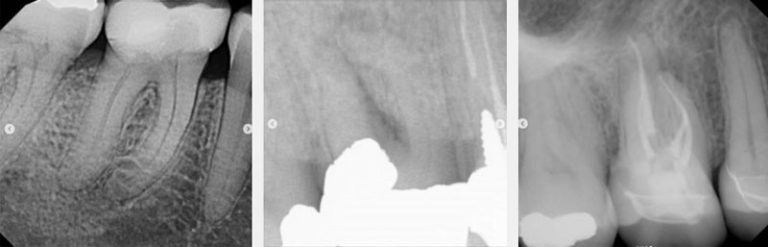

Identifying Pulpal Necrosis for Endodontic Treatment

Massachusetts-based endodontist Dr. Judy McIntyre provides three scenarios to help improve interdisciplinary patient care.By Judy McIntyre

Vertical Root Fractures: The Diagnostic Dilemma and Hidden Menace

Discover why early recognition of root fractures is necessary for the success of endodontic treatment.By Lou Berman

Invasive Cervical Root Resorption: The New Dental Epidemic?

Learn more about how to address invasive cervical root resorption, which is also known as extra-canal invasive root resorption, and…By Lou Berman